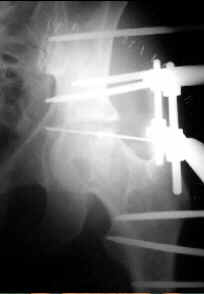

Treatment protocol included reduction on a traction table under general anesthesia. If good reduction is obtained, a pre-assembled frame is applied to do ligamentotaxis. If reduction is incomplete or impossible, open reduction and fixation of the displaced fragments is done with half cutted olive wires and then the frame is applied to do ligamentotaxis.

A) Post-operative Xr. B) Aspect of the frame. Total time with frame was 2 months. C) Xr control at 2 years of follow-up.